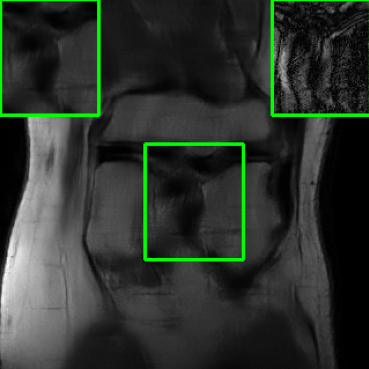

| Ground Truth | Vanilla MoDL | RS-E2E | SMUG |

![]() |

| PSNR = dB | PSNR = 23.41 dB | PSNR = 24.58 dB | PSNR = 28.91 dB |

| AT | Score-MRI | Deep-Equilibrium | Weighted-SMUG |

| PSNR = 28.67 dB | PSNR = 27.89 dB | PSNR = 24.13 dB | PSNR = 29.41 dB |

Results for the FastMRI Brain Dataset: we present the robustness results of the proposed approaches w.r.t. additive noise. In particular, the evaluation is conducted on the clean, noisy (with added Gaussian noise), and worst-case perturbed (using PGD for each method) measurements. Fig. 3 presents testing set PSNR and SSIM values as box plots for different smoothing architectures, along with vanilla MoDL and the other baselines using the brain dataset. The clean accuracies of Weighted SMUG and SMUG are similar to vanilla MoDL indicating a good clean accuracy vs. robustness trade-off. As indicated by the PSNR and SSIM values, we observe that weighted SMUG, on average, outperforms all other baselines in robust accuracy (the second and third set of box plots of the two rows in Fig. 3). This observation is consistent with the visualization of reconstructed images for the brain dataset in Fig. 4. We note that weighted SMUG requires longer time for training, which represents a trade-off. When comparing to AT, we observe that AT is comparable to SMUG in the case of robust (or worst-case noise) accuracy. However, the drop in clean accuracy (without perturbations) for AT is significantly larger than for SMUG. Furthermore, AT takes a much longer training time as it requires to solve an optimization problem (PGD) for every training data sample at every iteration to obtain the worst-case perturbations. Furthermore, we observe that its effectiveness is degraded for other perturbations including random noise as well as modified sampling rates shown in the next subsection. Importantly, the proposed SMUG and Weighted SMUG are not trained to be robust to any specific perturbations or instabilities, but are nevertheless effective for several scenarios.

Results for the FastMRI Knee Dataset: In Fig 5 and Fig 7, we report PSNR and SSIM results of different methods at two sampling acceleration factors for the knee dataset. Therein, we observe quite similar outcomes to those reported in Fig 3. Figs. 6 and 8 show reconstructed images by different methods for knee scans at 4x and 8x undersampling, respectively. We observe that SMUG and Weighted SMUG show fewer artifacts, sharper features, and fewer errors when compared to Vanilla MoDL and other baselines in the presence of the worst-case perturbations.